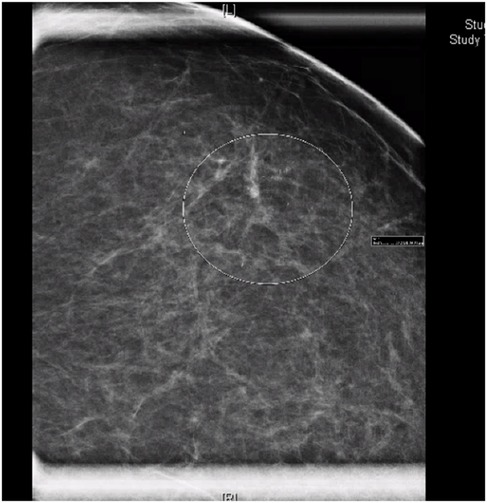

The patient presented in 2024, after a routine mammogram screening identified indeterminate calcifications in the upper outer quadrant of the left breast, classified as Breast Imaging-Reporting and Data System (BI-RADS) 0. She denied any nipple discharge, breast discomfort, or other abnormalities on self-breast exams. Three days later, a subsequent diagnostic mammogram identified a BI-RADS 4C lesion with a 3.4 cm area of calcifications in a linear and segmental distribution, 7.9–11.3 cm from the nipple (Figure 1).

Figure 1. Mammogram of left breast demonstrating linear and segmental punctate calcifications over a 3.4 cm area, mid-depth. BI-RADS 4C.